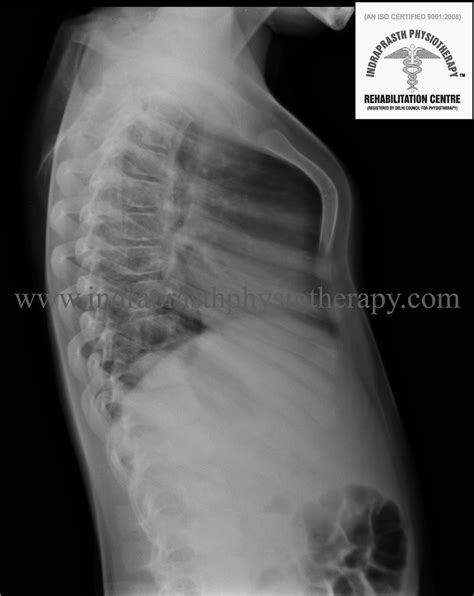

• Clinical Physical Exam: Assessment of chest symmetry and breathing patterns.

• Chest X-rays: Used to rule out heart or lung displacement.

• CT Scans or MRI: Reserved for more severe cases where surgery is being considered, helping to visualize the degree of deformity and impact on internal structures.

• Pulmonary Function Tests: To determine if the structural shape of the chest is limiting lung capacity or respiratory efficiency.